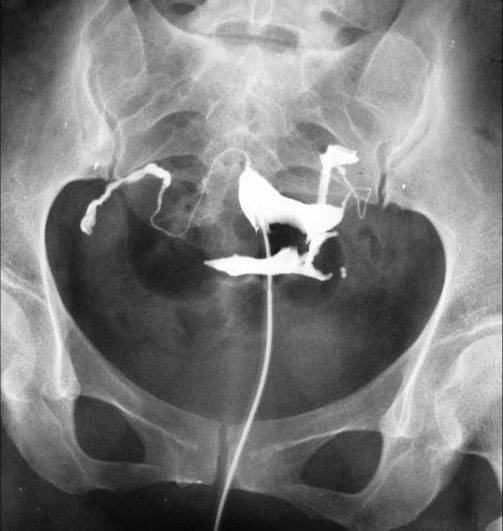

照片名称:子宫输卵管造影3

照片名称:子宫输卵管造影4

照片名称:子宫输卵管造影2

照片名称:子宫输卵管造影1

照片名称:子宫输卵管造影